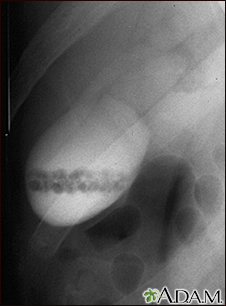

Cholecystogram